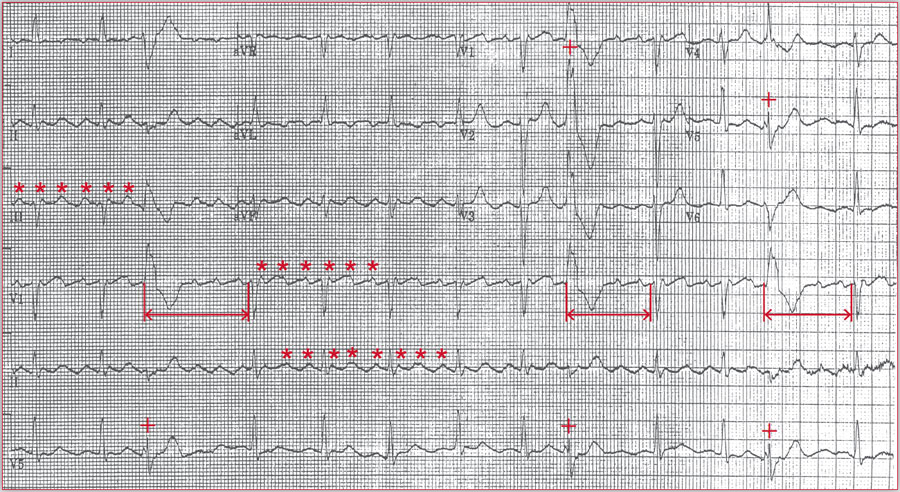

典型心电图分享:间位性室性早搏,可由劳累、情绪激动引起基础心律分析: 在这份心电图上,P波在Ⅰ、Ⅱ、aVF、V4-V6导联直立向上,avR导联向下,据此可判定其基础心律为窦性节律。 2、QRS波群分析: 第2、5、8个QRS波群宽大畸形,T波与主波方向相反,其前无相关P波,插入与正常窦性节律之间,由此判定其为间位性室性早搏。 3、临床症状分...